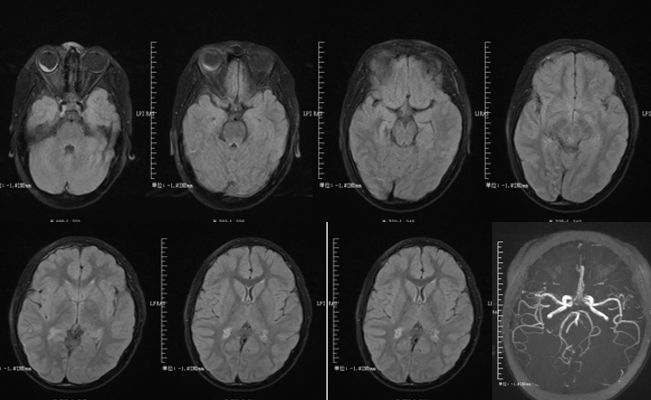

52岁,丙型肝炎患者,进行肝移植治疗肝硬化后使用免疫*制剂抑**等(他克莫司、霉酚酸酯、强的松)治疗。治疗3个月后出现间歇性头痛,复视(多为下视时出现),步态不稳,无全身症状。查体:血压136/73mmHg。眼球震颤,步态共济失调,腱反射正常。

答案:他克莫司相关神经毒性致脑干损伤。

补充辅助检查:血沉阴性,C-反应蛋白,艾滋病毒、半乳甘露聚糖、1,3-b-D-葡聚糖、隐球菌,结核均阴性。脑脊液中有1个白细胞,蛋白质101 mg/dL,革兰氏阴性染色,细菌性真菌培养,EB病毒,巨细胞病毒,单纯疱疹病毒,人类疱疹病毒6型,JC病毒,以及寡克隆带均阴性。免疫球蛋白G指数为正常。胸片呈阴性。脑PET扫描未发现PET摄取异常。在患者住院期间,他克莫司的治疗剂量为6.3~9.0ng/ ml。经治医生不排除他克莫司导致脑干脑炎的可能,并将药物改为环孢菌素。患者入院2周和6周各进行了一次MRI 检查,结果显示脑干病变较前好转 (图B、C)。6个月后随访,患者的神经系统检查和MRI 均未见明显异常。B为他克莫司停药后2周MRI。C为 6周后脑磁共振Flair图像。

他克莫司是抑制神经钙蛋白磷酸酶活性和T淋巴细胞化的免疫*制剂抑**。可引发一系列神经系统的不良反应,包括轻微头痛、震颤痫性发作、皮质性失明和昏迷,且不良反应的发生与他克莫司剂量无相关性。

当患者出现T2及Flair序列的脑桥高信号时,要考虑到他克莫司神经毒性导致脑干脑炎的可能。